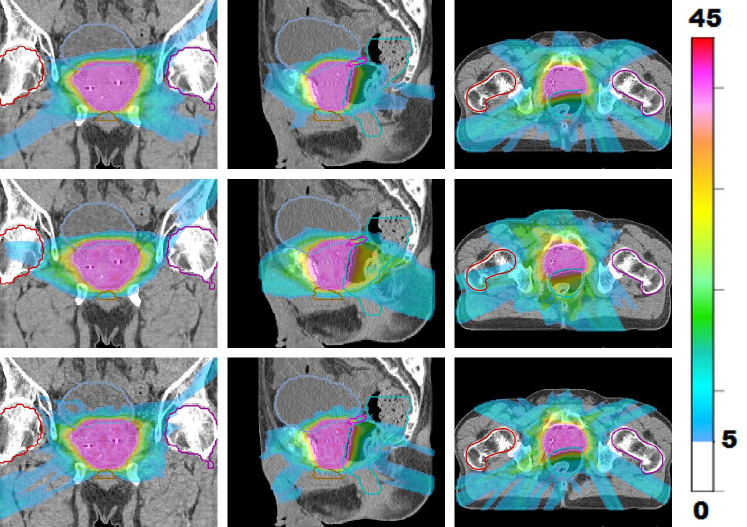

Figure 1: LABEL:sub@prt_allFracs and LABEL:sub@lng_allFracs Fraction-variant treatment plans for each of five fractions for cases “PRT” and “LNG”. The PTV receives a uniform dose of 888 Gy (approximately) at each fraction for case “PRT” and 9.6 Gy (approximately) for case “LNG”. LABEL:sub@hnk_allFracs Dose colormaps for fractions 1, 7, 13, 19, and 25 for case “H&N”. The PTV receives a uniform dose of 2.2 Gy (approximately) throughout the treatment course.

Figure 1LABEL:sub@prt_allFracs shows dose colormaps for each of the five fractions for the FV prostate plan. Notice that despite the variation in dose distributions, the PTV is covered uniformly in all fractions. Each voxel in the PTV receives a dose of approximately 40/5=8405840/5=8 Gy per fraction. Figure 2 visualizes the beam angles that were selected for each of five fractions for the prostate case using the FV BOO algorithm. Each beam is specified by a couch angle and a gantry angle. The FV BOO algorithm selected 9.6 beams per fraction, on average. As expected, the algorithm did not select the same set of beam angles for each fraction. In fact, a total of 44 distinct beam firing positions were utilized, as visualized in figure 2LABEL:sub@prt_beams_allFracs.

Figure 3 shows the total dose distribution, summed over all five fractions, for the FV plan (top row) as well as a conventional 10-beam FI plan (middle row) and a conventional 20-beam FI plan (bottom row). Corresponding dose-volume histograms, comparing the FV plan with the two FI beam plans, are shown in figure 4. Compared with the 10-beam FI plan, the FV plan achieves dosimetric improvements for all OARs except the left femur, which receives similar low doses in both plans. The dosimetric improvement to the anterior rectum is particularly evident. Mean dose was reduced by 5.7 Gy (rectum), 4.6 Gy (penile bulb), 4.3 Gy (seminal vesicle), and 1.4 Gy (bladder). Max dose was reduced by 6.0 Gy (right femur), 3.3 Gy (penile bulb), and 1.3 Gy (seminal vesicle). The PTV coverage is more homogeneous for the FV plan. The dosimetric quality of the FV plan is similar to that of the 20-beam FI plan, despite the fact that the FV plan uses only half as many beams per fraction.

Figure 3: Visualizing the dose distribution (summed over all five fractions) for FV plan using average of 9.6 beams per fraction (top row) as well as a 10-beam FI plan (middle row) and a 20-beam FI plan (bottom row). Dose below 5 Gy is not shown.